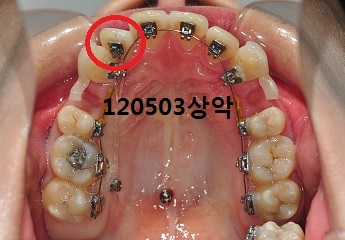

이번 월치료에는 상악 어금니에 탈락되었던 브라켓을 부착하고 상악에 와이어 교체, 고무줄 교체가 이루어졌어요.

세 달 전쯤인가 과자를 먹다가 상악 어금니에 브라켓이 탈락되어었는데요,

초기 단계라 급하게 부착할 정도는 아니여서 이번에 부착해주셨어요^^

상악

앞니부분에 고무줄연결을 해주셨어요.